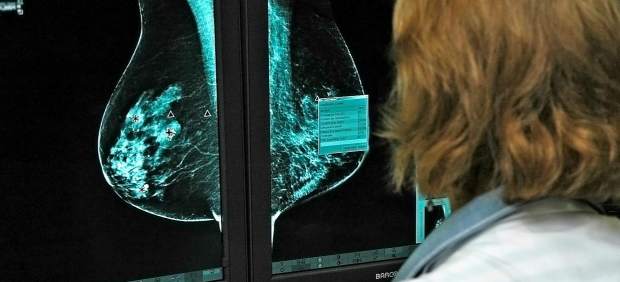

Un equipo multidisciplinar de científicos ha conseguido demostrar, tras cinco años de investigación y la colaboración de 38 hospitales españoles, el nexo que existe entre el cáncer de próstata más agresivo y el cáncer de mama hereditario.

El cáncer de próstata más agresivo, uno de los tumores que más muertes causan en hombres, se asocia —han concluido los investigadores— con mutaciones del gen BRCA2, un gen que a su vez está relacionado también con el cáncer de mama hereditario, con el de ovario y con el de páncreas.